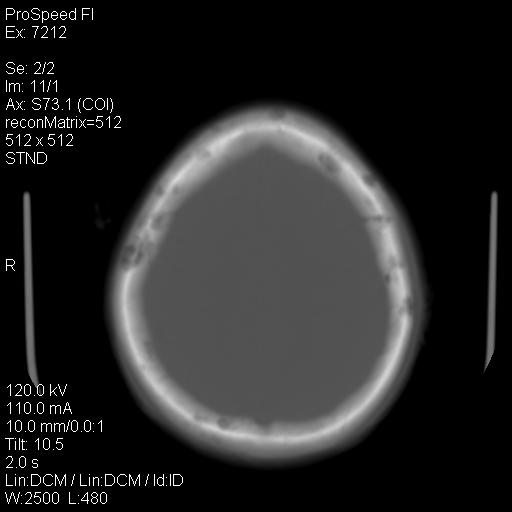

右额叶脑沟变浅,脑表面见新月形稍高密度影,考虑慢性硬膜下出血可能。

额顶骨多发穿凿样骨缺损区,不排除骨髓瘤等改变,进一步检查。

额顶骨多发穿凿样骨缺损区,不排除骨髓瘤或嗜酸性肉牙肿等改变,进一步检查。

1)右侧半卵圆中心腔隙性脑梗塞。2)考虑左侧额部慢性硬膜下血肿(或硬膜下积液)。3)颅骨骨髓瘤不排除;建议行进一步检查。